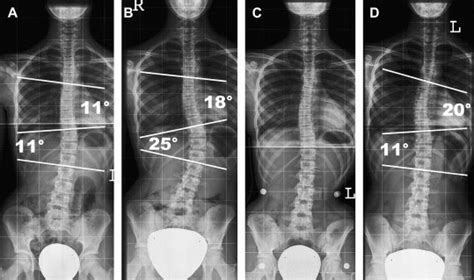

Alright, let’s break down what typically goes into a scoliosis radiology program . It’s not a one-size-fits-all deal, but most programs will focus on a few key areas to ensure practitioners are well-equipped. First off, imaging modalities are central. This means getting hands-on (or at least deeply familiar) with X-rays, specifically full-spine standing X-rays, which are the gold standard for initial assessment. We’re talking about understanding radiation dose, patient positioning for optimal views (like AP - anterior-posterior, and lateral), and the specific markers used to measure curves, like the Cobb angle. Beyond X-rays, depending on the program and the suspected cause, you might delve into CT scans for detailed bone structure and MRI for soft tissues, nerves, and spinal cord evaluation. The interpretation of images is another massive chunk. This involves learning to identify the type of scoliosis – idiopathic (most common, cause unknown), congenital (born with it), or neuromuscular (due to nerve or muscle conditions). Radiologists need to meticulously measure curve magnitudes, look for rotational changes, and assess vertebral body abnormalities. They’re trained to spot red flags that might suggest conditions like spinal tumors or infections, which can mimic scoliosis. Radiation safety is non-negotiable, guys. Protocols for minimizing radiation exposure to patients, especially children who are more sensitive, are heavily emphasized. This includes using the lowest effective dose settings and appropriate shielding. Finally, patient interaction and communication are often included. While radiologists are primarily behind the scenes, understanding how to communicate findings to referring physicians, and sometimes directly to patients or their families, is a vital skill. This often involves clear explanations of what the images show and the implications for treatment. Some advanced programs might even touch upon newer technologies like EOS imaging systems, which provide low-dose, 3D imaging of the entire skeletal structure. It’s a comprehensive education aimed at producing experts who can provide the clearest possible picture of a patient’s spinal health. The continuous evolution of imaging technology means these programs are also constantly updated to include the latest advancements, ensuring that the practitioners are always at the forefront of diagnostic capabilities. This dedication to comprehensive training ensures that every scan contributes meaningfully to patient care.

So, why the fuss about specialized training, you ask? Why can’t any radiologist just look at a spine X-ray? Well, the spine is a complex beast, and scoliosis imaging requires a level of detail and understanding that goes beyond a general radiological assessment. Specialized training in scoliosis radiology ensures that the professionals viewing these images possess a deep understanding of spinal anatomy, biomechanics, and the various pathologies that can lead to spinal curvature. For instance, recognizing the subtle differences between a simple idiopathic curve and one caused by a congenital anomaly requires specific knowledge. The measurement of curves, most notably the Cobb angle, needs to be precise. Small variations in measurement technique can lead to significant differences in perceived curve progression, impacting treatment decisions like whether surgery is needed. Radiologists trained in scoliosis protocols know exactly how to take these measurements consistently and accurately. Furthermore, scoliosis often affects developing children and adolescents. This means radiologists must be acutely aware of growth plates, skeletal maturation (using tools like the Risser sign), and how these factors influence curve progression and treatment outcomes. They need to consider the long-term implications of imaging findings on a growing body. Radiation dose optimization is another critical aspect where specialized training shines. Children are more vulnerable to the effects of radiation, so minimizing exposure while obtaining diagnostic-quality images is paramount. Specialized programs teach techniques and protocols specifically designed for pediatric patients, ensuring they receive the safest possible imaging. Think about it: a standard chest X-ray protocol is vastly different from a scoliosis series. The technologists and radiologists in these programs are trained to administer the right amount of radiation, just enough to see what they need to see, and no more. This careful balance is a hallmark of expert care. Without this specialized knowledge, there’s a risk of misinterpretation, inaccurate measurements, delayed diagnosis, or even unnecessary radiation exposure. It’s about ensuring that every imaging study provides the maximum benefit with the minimum risk, ultimately contributing to better patient outcomes and a more confident approach to managing scoliosis. The expertise gained here is not just about reading scans; it’s about understanding the patient’s entire clinical picture and how the imaging fits into the broader management strategy. This holistic view is what differentiates a general radiologist from a scoliosis imaging specialist.